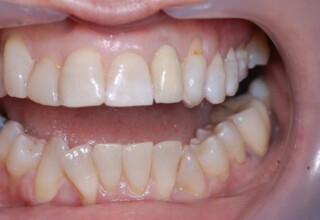

Restoration of bilateral diastemas between central and lateral incisors.

Diastemas were created mainly because of narrow laterals. After orthodontic treatment was finalized, the diastemas were closed with two composite resin restorations.